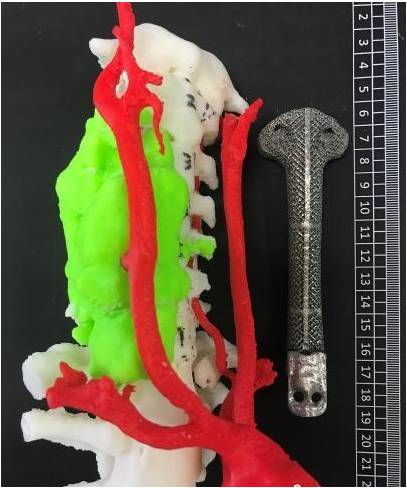

Instant and interactive surface extraction and export to STL and PLY formats.